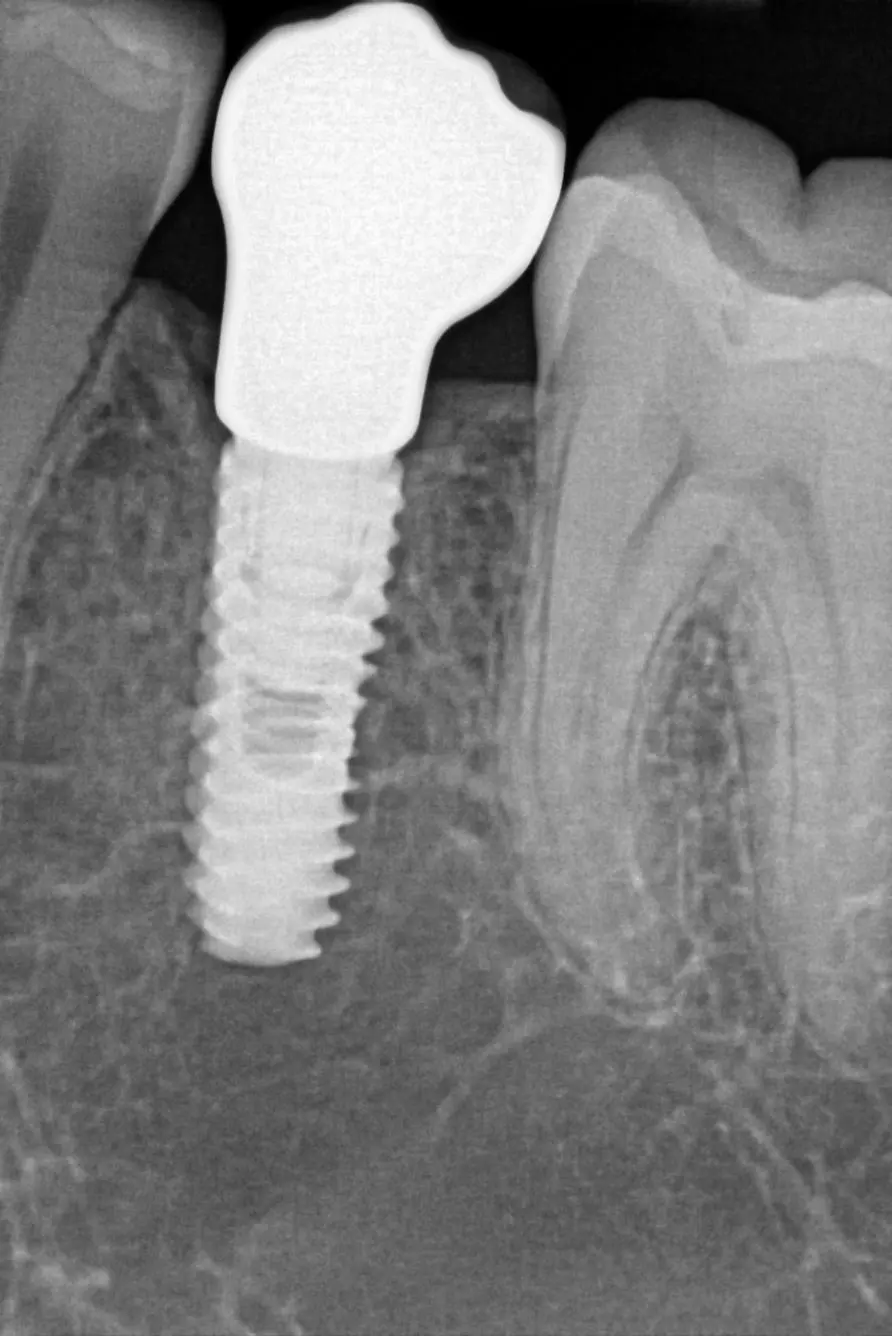

RTG intraoralna slika dentalnog implantata

Protetična oskrba po vstavitvi vsadkov

Ko se vsadek popolnoma zraste s kostjo, sledi protetična faza.

• Če manjka en zob, se izdela krona na vsadku.

• Če manjka več zob, se izdela mostiček na vsadkih.

• Če manjkajo vsi zobje, se izdela mostiček ali proteza z lokatorji.

Spoj med vsadkom in krono se imenuje nadgradnja (abutment). Kronice in mostičke najpogosteje izdelujemo iz cirkon-oksidne keramike – izjemno trpežnega, biokompatibilnega in estetsko naravnega materiala. Posebno pozornost namenjamo delu krone med zobom in dlesnijo, saj ta del močno vpliva na dolgotrajnost vsadka.